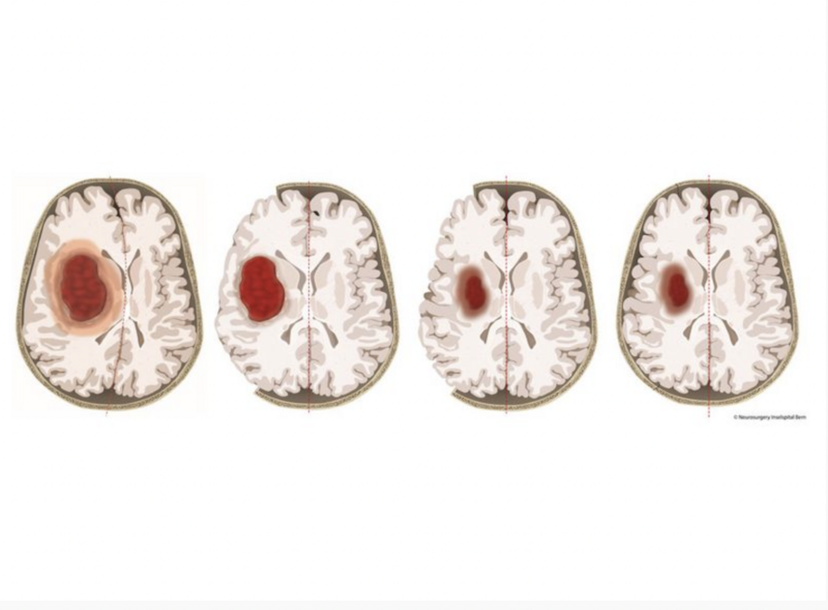

Um schwere Druckschäden nach einer Hirnblutung zu verhindern, haben die Ärztinnen und Ärzte in der Studie temporär einen Teil des Schädelknochens entfernt. Nach dem Abschwellen – meist nach einigen Wochen – wurde der Knochen wieder implantiert. Abbildung: Universitätsklinik für Neurochirurgie, Inselspital Bern

Bei der dekompressiven Kraniektomie wird ein Stück der Schädeldecke chirurgisch entfernt, um den erhöhten Hirndruck zu senken. Bei Patientinnen und Patienten mit ischämischem Hirninfarkt führt dieses Verfahren nachweislich zu besseren Langzeitergebnissen. Für Patientinnen und Patienten mit einer Hirnblutung ist SWITCH die erste Studie, die das untersucht. Sie wurde hauptsächlich vom Schweizerischen Nationalfonds und der Schweizerischen Herzstiftung finanziert.